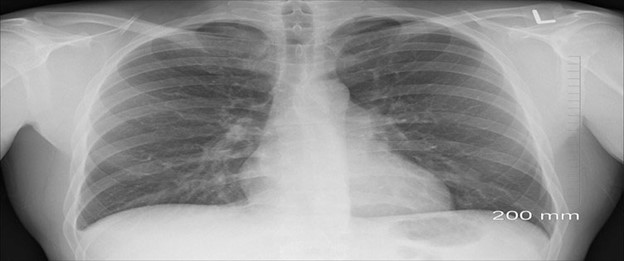

Desde 1986, el Departamento Estatal de Servicios de Salud (DSHS) de Texas ha realizado un seguimiento de la asbestosis y la silicosis en el estado. La asbestosis es una enfermedad pulmonar fibrótica crónica. Se produce por la inhalación prolongada de fibras de asbesto respirables. La silicosis es una enfermedad respiratoria. Se produce por la inhalación prolongada de polvo de sílice cristalina respirable.